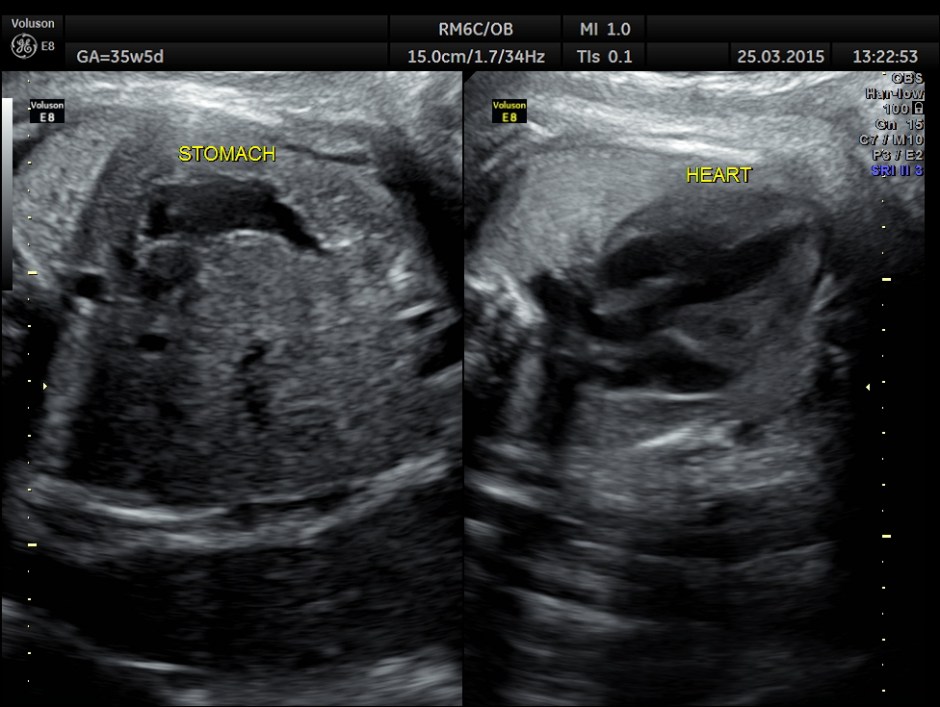

The following picture shows a normal situs and axis . The great vessels running parallel are also seen.

This shows normal veno atrial and atrial ventricular connections ( concordance ) and ventricular arterial switched connections (discordance).